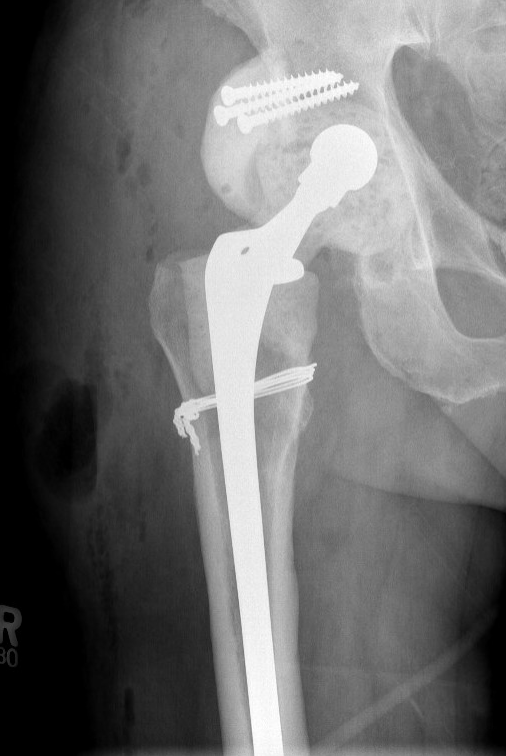

Two-Stage Revision

Technique

First stage

- debridement + removal of implants and all cement

- insert antibiotic impregnated cement spacer

Second stage

- definitive revision

- at least 2 - 4 weeks off antibiotics and normal CRP / ESR

- consider hip aspiration

- intra-operative FFS at time of surgery